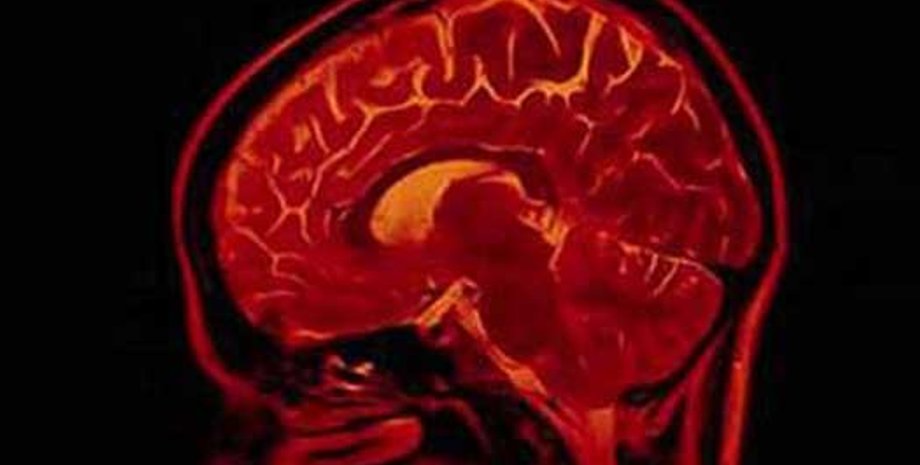

В своей работе ученые сравнили томограммы головного мозга, сделанные с помощью метода функциональной магнеторезонансной томографии, у 20 бывших партизан, прошедших курс обучения грамоте и 26 партизан, которым освоить грамоту еще только предстояло. Таким образом, ученые обнаружили области мозга, вовлеченные в процесс чтения.

Области, отвечающие за грамотность, оказались сконцентрированы в нескольких областях левого полушария мозга. Плотность серого вещества, отвечающего за обработку информации, оказалась увеличенной после обучения чтению в областях, уже выявленных учеными прежде как области, отвечающие за распознавание букв, их преобразование в звуки и осмысленные слова и фразы.

Кроме того, ученые обнаружили, что плотность белого вещества, отвечающего за связь между этими долями, тоже возрастает по мере обучения грамоте.

Особенно сильно увеличились "контакты", приходящие и исходящие из угловой извилины. В течение 150 лет ученые знали, что эта область мозга каким-то образом связана с грамотностью, однако установить ее точную функцию за полтора века никто не смог.